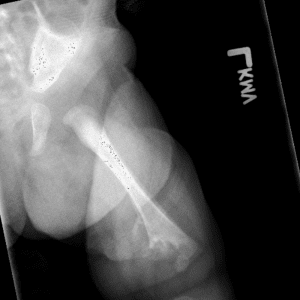

Pediatric Radiographs